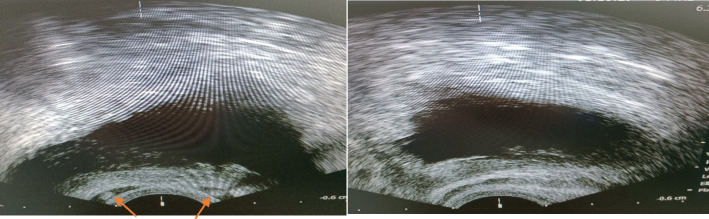

Methods: In this multi-center, retrospective cross-sectional study, we reviewed data from 47 CBAVD patients diagnosed between 1994 and 2024. Data collected included demographic information (age, height, weight, BMI), physical examination findings (vas palpation), and imaging results (trans-rectal ultrasound for seminal vesicle status, abdominal and pelvic ultrasound for kidney status). Laboratory data included serum FSH, LH, and testosterone levels, as well as semen analysis results (pH, fructose, and volume). Patients were classified into three groups based on seminal vesicle status: bilateral agenesis, unilateral agenesis, and bilateral presence.

Abstract Image